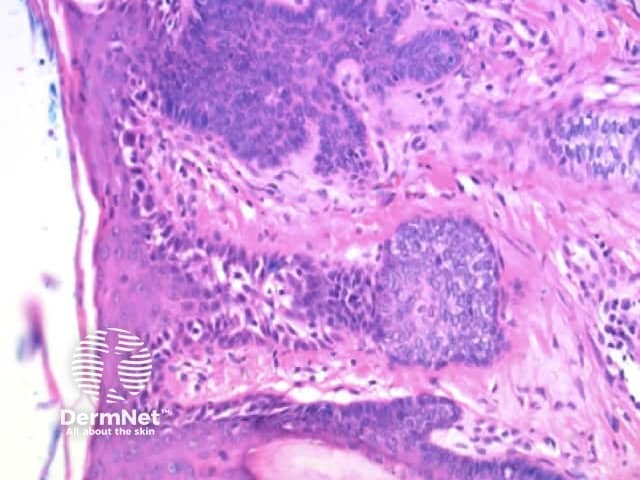

Clods are solid rounded structures of sufficient size to show an appreciable variability in size. Their colour depends on the nature and, in the case of melanin, depth of the substance they comprise (Figures 37-50). Other terms have been used for clods in specific settings such as blue-grey ovoid nests for grey and / or blue clods seen in basal cell carcinoma.

Figure 48. Diagram. Brown, grey and blue clods are due to nests of melanin-containing cells at different levels in the skin. From Kittler et al (1).

Figure 49a Figure 49b Figure 49c Figure 49d

Figure 50a Figure 50b